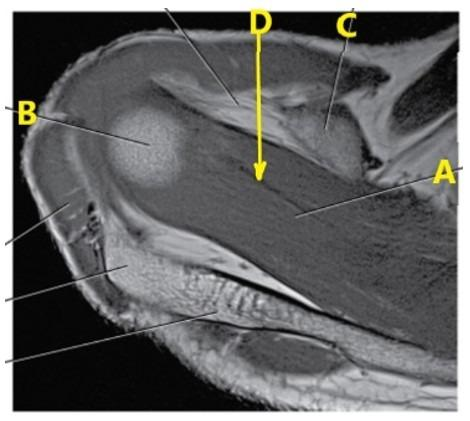

What is letter D arrow pointing to?

Supraspinatus tendon

Medial meniscus

The oblique coronal views for an MRI of the shoulder need to be oriented ---

Parallel to the supraspinatus tendon

Which rotator cuff tendon is the most frequently injured?

Supraspinatus